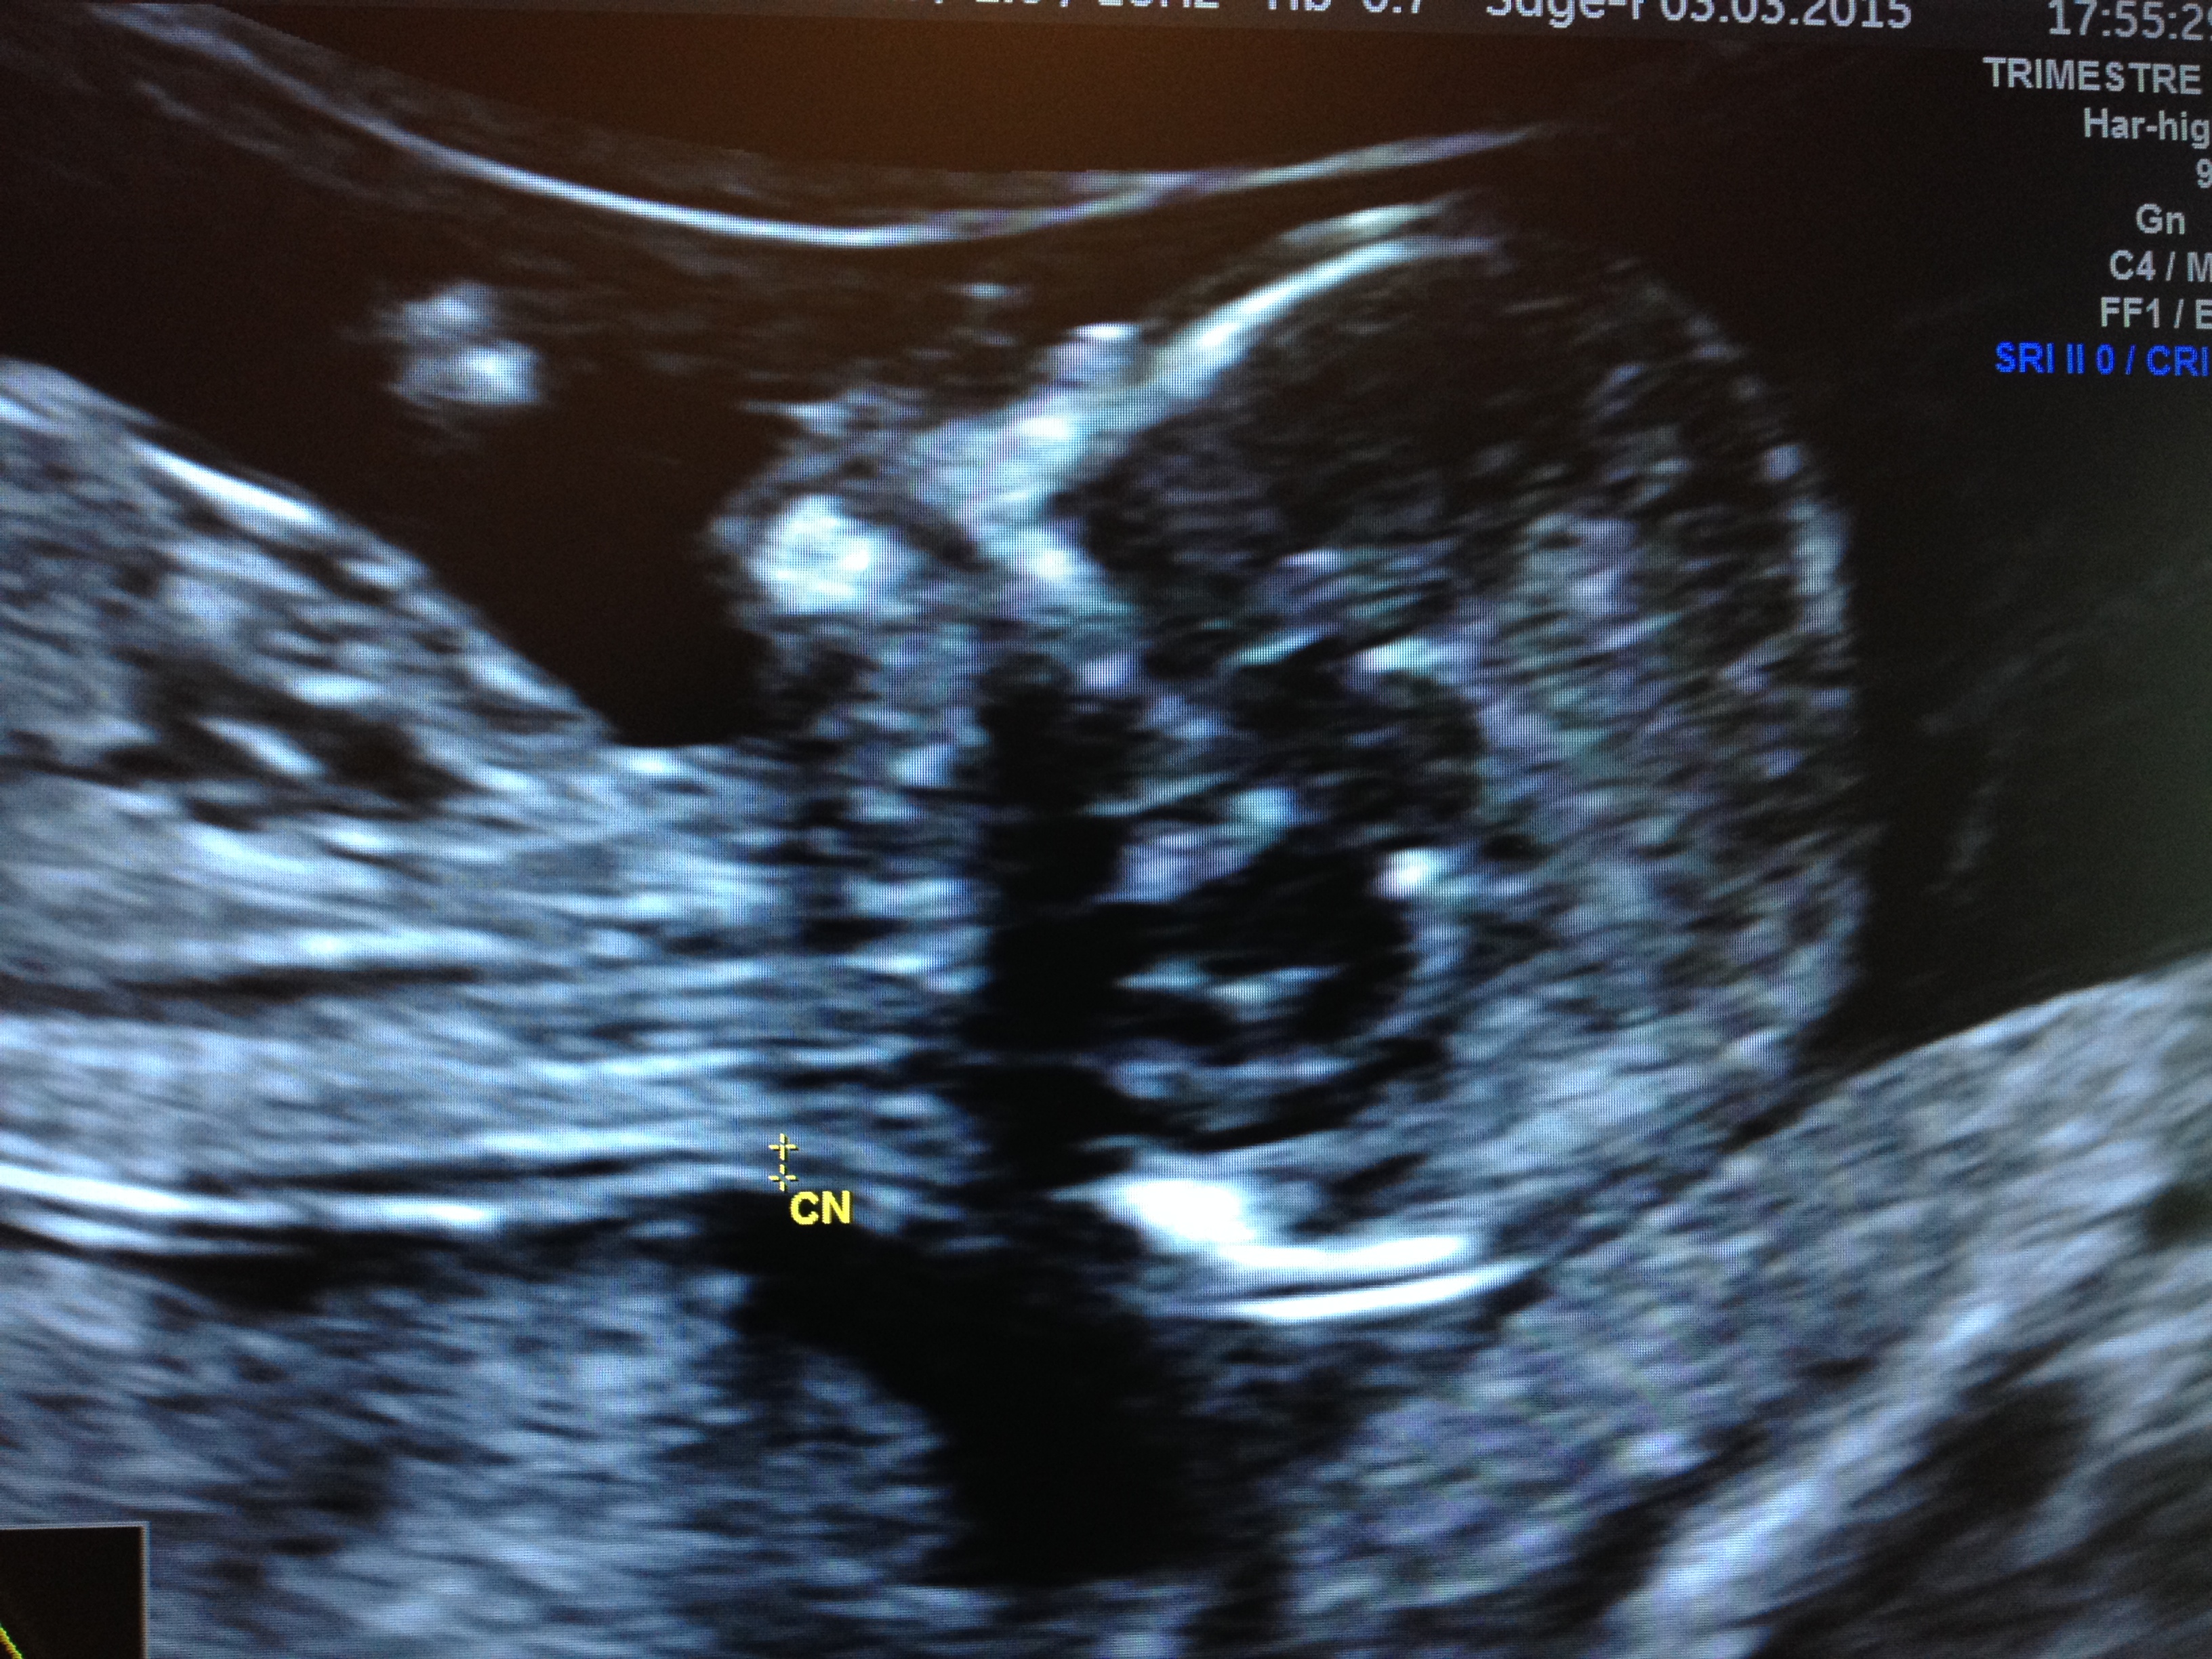

1-Echographie de 12 sa

Elle a pour objectif de dater précisément la grossesse, compter le nombre d'embryons, vérifier l'absence de graves malformations précoces, mesurer la clarté nucale.

n.b: La clarté nucale est un signe d'appel échographique d'anomalie des chromosomes (dont la trisomie 21), pour être fiable, celle-ci doit être mesurée avec des critères précis. Il existe une accréditation qui permet de relier cette mesure à une prise de sang  qui précise encore le risque d'anomalie des chromosomes. Je possède cette accréditation.